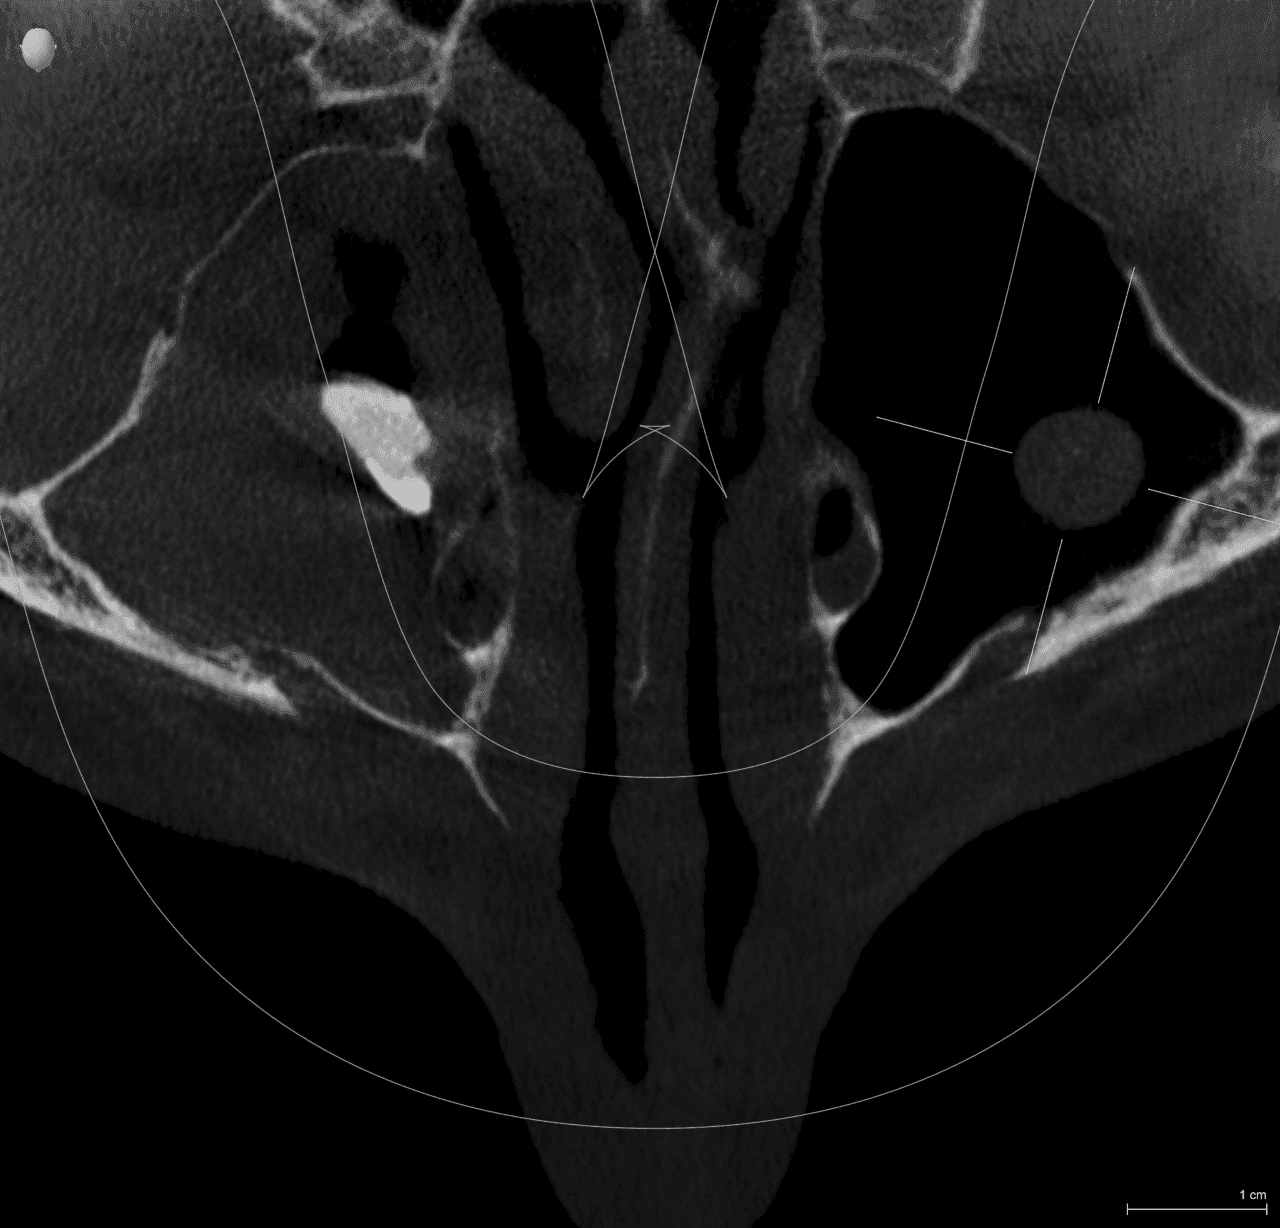

Fig. 3. Corte axial donde se puede apreciar el órgano dentario dentro del seno maxilar.

- Se reflejó el colgajo con un levanta periostio molt número 9 y se procedió a realizar el abordaje de Cadwell luc, mediante una pieza de mano de baja velocidad y una fresa quirúrgica #703. (Figs. 4 y 5)